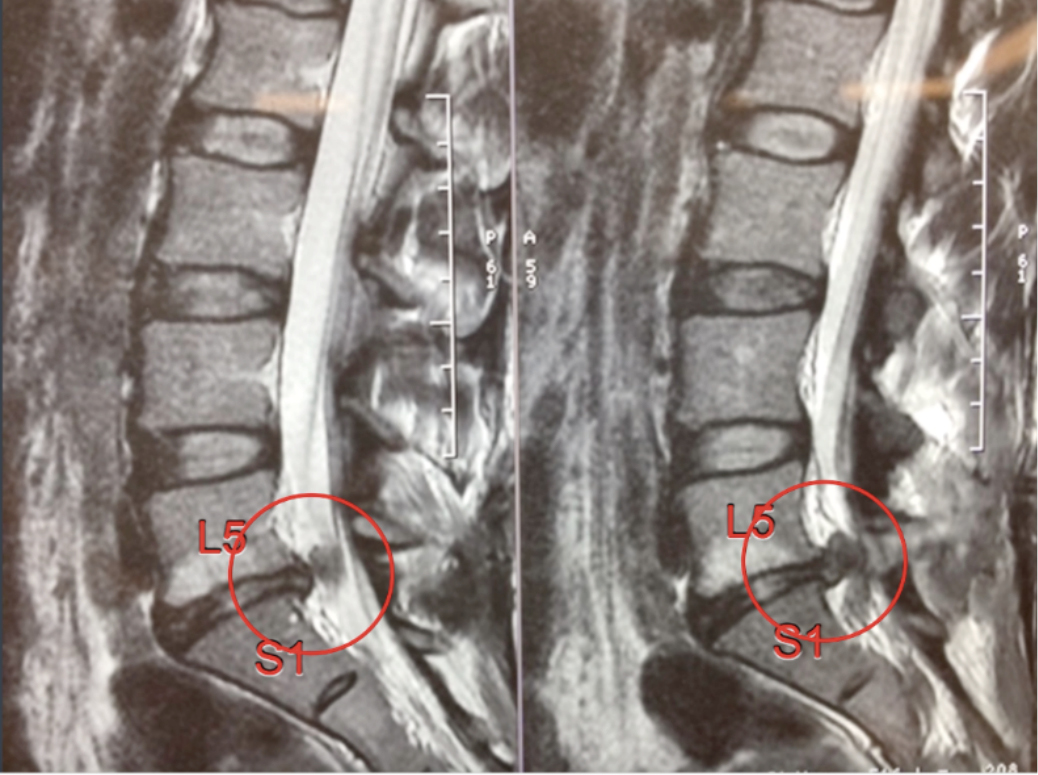

Структура позвоночника: сегменты и тазовые отделы в фотографиях